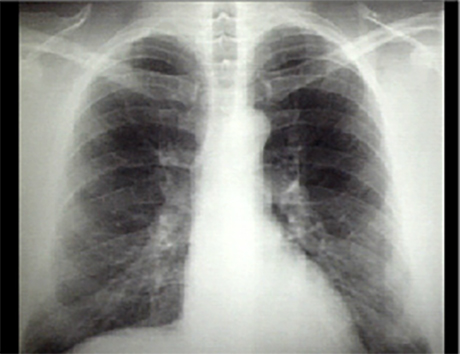

You are incorrect - The best interpretation of the chest X rays in our patient is that they are normal.

Your choice: Normal with bilateral accessory rib

This chest X ray shows bilateral accessory ribs. In this PA view, they are demonstrated by the bilateral small curved osseous structures that originate above the first rib posteriorly and extend anteriorly. In this view, they overlie the lung apices.